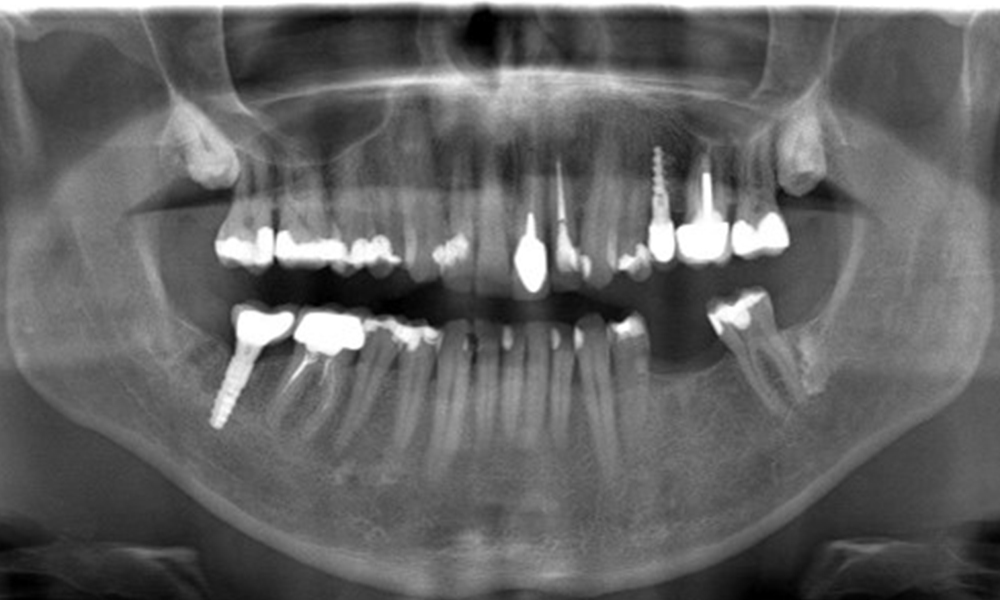

В медицинската история 55-годишният пациент заявява, че няма хронични заболявания и не приема никакви лекарства. Начинът на живот на пациента също е без забележки. Пациентът има няколко зъбни възстановявания и два импланта (2-ри и 4-ти квадрант). Въз основа на настоящите данни се установява гингивит при иначе стабилно пародонтално състояние върху редуцирания пародонт (стадий III, степен А).

OPG: 29/02/2024